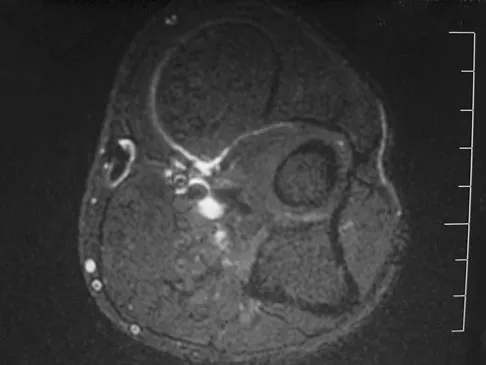

Figures 27a through 27c show the AP radiograph, MRI scan, and biopsy specimen of an otherwise healthy man who has a painful wrist. Serum chemistry studies are normal. What is the most likely diagnosis?